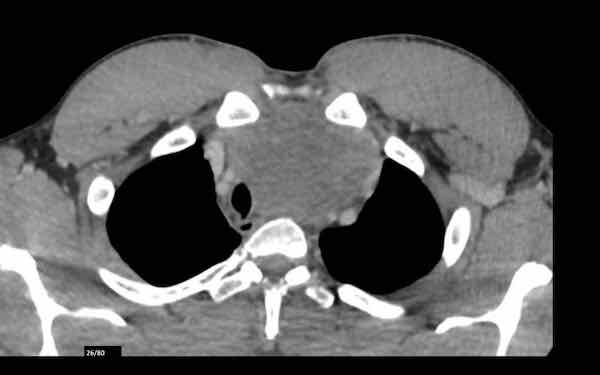

U thần kinh nội tiết tuyến ức

Ca lâm sàng

Các hình ảnh này của một bệnh nhân nam 36 tuổi bị hội chứng Cushing, đã được phẫu thuật cắt bỏ u tuyến yên.

Tuy nhiên, hội chứng Cushing vẫn tồn tại và phát hiện một khối ở trung thất.

Hình ảnh

Khối đặc với vôi hóa trung tâm (mũi tên đen).

Lưu ý bờ khối không đều ở phía bên trái.

Hạch bạch huyết thượng đòn trái to (hạch Virchow: mũi tên trắng).

Đây không phải là PET-CT thông thường mà là PET Dotatoc, được sử dụng để phát hiện u thần kinh nội tiết và các tổn thương di căn của chúng.

Có nhiều tổn thương di căn xương (mũi tên).

Chẩn đoán cuối cùng

U thần kinh nội tiết tuyến ức (NETT)

U thần kinh nội tiết tuyến ức là các u hiếm gặp.

Chúng có tính chất rất xâm lấn và thường biểu hiện với sự xâm lấn các cấu trúc trung thất xung quanh, đồng thời liên quan đến các bệnh lý nội tiết như hội chứng Cushing, to đầu chi (acromegaly) và hội chứng MEN-1.